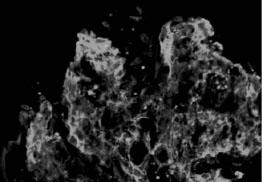

光镜下,大多数患者肾小球呈内皮细胞、系膜细胞弥漫性急性增殖,少数以渗出病变为主,另有少部分呈系膜、毛细血管型病变(膜增殖型病变),严重时增生的系膜可将肾小球分隔成小叶状,偶有球囊新月体形成。电镜可见上皮下电子致密物呈驼峰状沉积,为本病的特征。但这一变化消失较快,发病3个月后即不易见到,这些沉积物多在上皮侧,有时在内皮下。免疫荧光检查,内含有免疫球蛋白,主要是IgG、IgM、IgA也可见到,同时也可有C3沉积,有时尚可见到链球菌抗原在系膜区沉积物中。见图2—1、图2—2、图2—3。

图2—3 毛细血管内增生性肾小球肾炎,IgG呈颗粒状沉积于毛细血管壁(免疫荧光 x400)